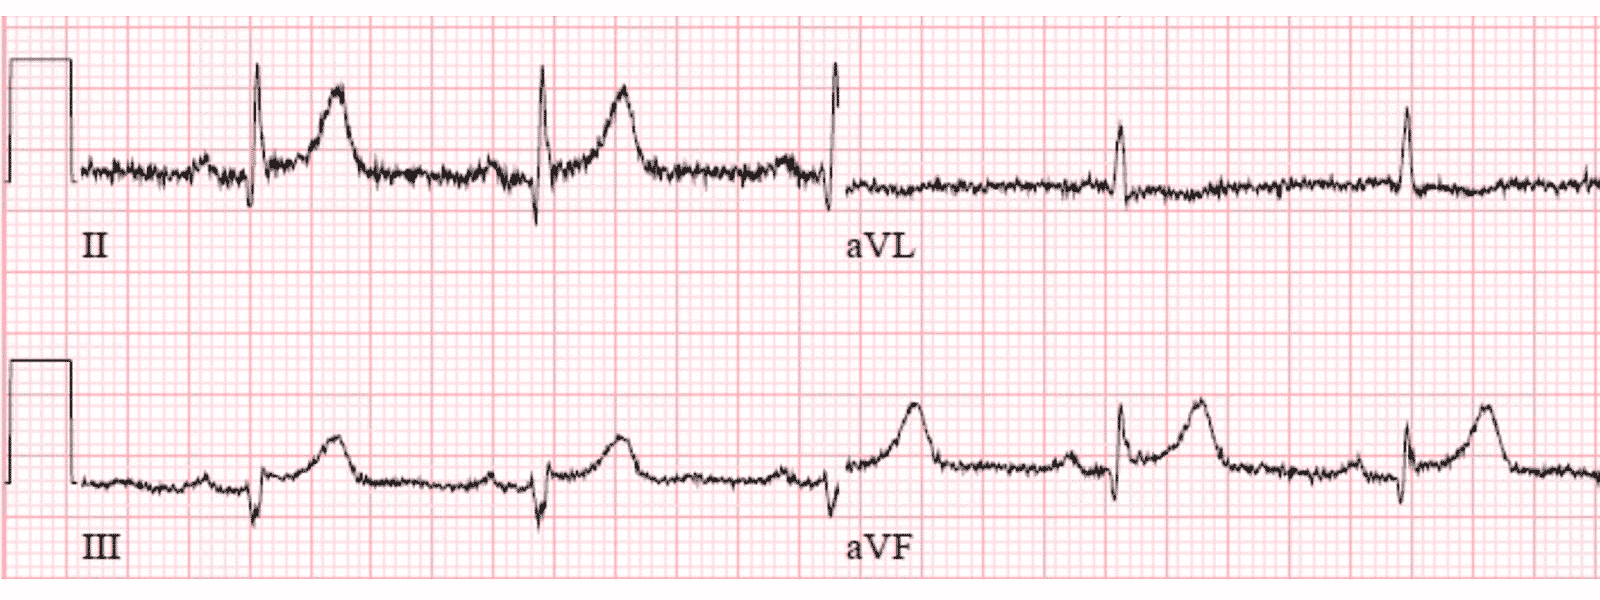

Она была доставлена в отделение неотложной помощи, где и была записана эта ЭКГ (она все еще чувствовала тошноту, но боли в груди, одышки или других симптомов не было):

- Синусовый ритм

- Весьма нормальный комплекс QRS

- Элевация ST менее 1 мм во II, III и aVF, а также V4-6, все с выраженной выпуклостью вниз (седловидные)

- В aVL, возможно, имеется небольшая депрессия ST с неглубоким отрицательным зубцом Т

- Зубцы Т в нижних отведениях, кажется, имеют потенциально большую амплитуду по сравнению с предшествующим им комплексам QRS

- Критерии ИМпST не выполняются

- В нескольких отведениях имеются артефакты изолинии. На ЭКГ № 1 это наиболее заметно в отведениях II, III и aVF. Поскольку электрод от левой ноги этих 3 отведений является общим для этих отведений, это вероятный источник этих артефактов. Подчеркну, что, несмотря на артефакты, эта ЭКГ совершенно отчетливо интерпретируема. Причина, по которой я обращаю внимание на артефакт, заключается в том, что в случаях, когда артефакты ухудшают интерпретацию, может быть полезно определить, из-за какого электрода возникает артефакт.

- Есть несколько маленьких и узких зубцов Q. Они видны в отведениях I, II, aVL, aVF; и V3-V6. Кажется, что в отведении III имеется малюсенький, но совершенно отчетливый начальный зубец r. Клиническое значение этих Q неопределенно, но их присутствие следует отметить, потому что эта находка может быть актуальной, если бы был развивающийся инфаркт.

- Имеется ранняя переходная зона - потому что зубец R становится доминирующим (т. е. больше, чем амплитуда S) уже в отведении V2. Эта находка также может быть актуальной, потому что задний инфаркт является одной из возможных причин формирования ранней переходной зоны.

- В нижних и боковых грудных отведениях наблюдается элевация ST менее 1 мм.

- Имеется уплощение сегмента ST с минимальной инверсией зубца Т в отведении aVL. Отведение aVL не показывает истинной «реципрокности».

- Зубцы T в нижних отведениях ЭКГ №1 выше, чем ожидалось, учитывая картину комплекса QRS в каждом из этих отведений.

- На ЭКГ №1 критерии ИМпST определенно не выполняются.

- Зубцы Т в каждом из нижних отведений ЭКГ № 1 не такие «жирные», как зубцы Т-волны в истинно позитивном примере нижних острейших Т, которые доктор Мейерс показал выше.